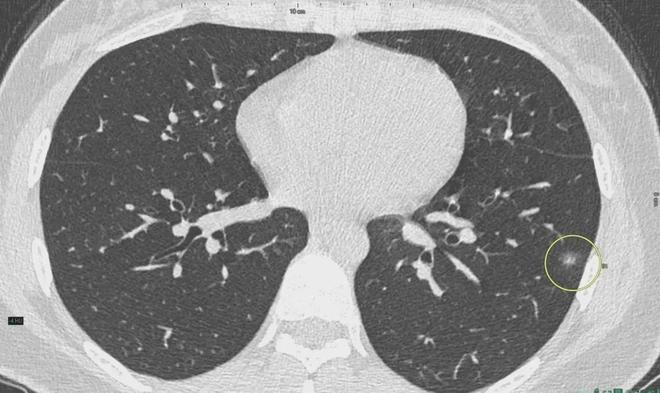

肺結(jié)節(jié)是一種常見的肺部疾病,其發(fā)病率逐年上升,雖然肺結(jié)節(jié)多數(shù)情況下是良性的,但也有可能惡化為肺癌,了解肺結(jié)節(jié)的形成原因?qū)τ陬A(yù)防和治療具有重要意義,本文將為您詳細解析肺結(jié)節(jié)的形成機制。

肺結(jié)節(jié)的形成原因

3、生活習慣

生活習慣對肺結(jié)節(jié)的形成也有一定影響,長期吸煙是肺結(jié)節(jié)形成的重要危險因素之一,煙草中的有害物質(zhì)會對肺部造成損傷,導(dǎo)致肺部細胞異常增生,長期熬夜、飲食不規(guī)律等不良生活習慣也可能影響肺部健康,增加肺結(jié)節(jié)的發(fā)病風險。